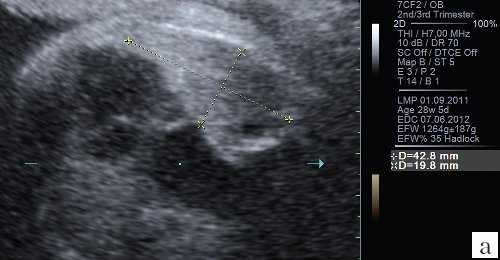

Для уменьшения расхождения в оценке ЛГО в норме и при диафрагмальной грыже группой авторов под руководством С. Peralta и K. Nikolaides [2] произведено сравнение возможных методов измерения легких. Было доказано, что метод трассировки (длина контура) дает наименьшие расхождения в измерениях между специалистами; метод двух перпендикуляров (перемножение максимальных диаметров) является наиболее популярным, но в неопытных руках может существенно (до 45%) завышать размеры легкого, метод с включением в расчет переднезаднего размера легкого наименее воспроизводим, поскольку нет точных ориентиров установки калиперов переднезаднего размера (рис. 3).

а) Метод трассировки.

б) Метод двух перпендикуляров (метод максимальных диаметров).

в) Метод оценки переднезаднего размера.

Этими же авторами были разработаны номограммы площади и ЛГО для правого и левого легкого в норме для каждой недели беременности с 12 нед до 32 нед (табл. 1) и дополнительно предложены формулы для расчета нормальной для срока площади легкого при любом из указанных трех способов измерения (табл. 2).